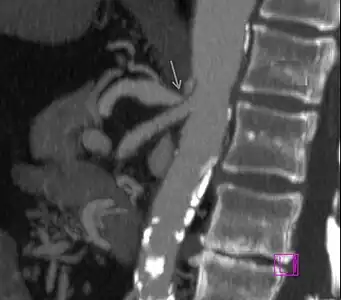

Further evaluation and confirmation can be obtained via angiography to investigate the anatomy of the celiac artery.[5] Historically, conventional angiography was used, although this has been largely replaced by less invasive techniques such as computed tomography (CT) and magnetic resonance (MR) angiography.[2][5] Because it provides better visualization of intra-abdominal structures, CT angiography is preferred to MR angiography in this setting.[5] The findings of focal narrowing of the proximal celiac artery with poststenotic dilatation, indentation on the superior aspect of the celiac artery, and a hook-shaped contour of the celiac artery support a diagnosis of MALS.[2] These imaging features are exaggerated on expiration, even in normal asymptomatic individuals without the syndrome.[2]

Proximal celiac artery stenosis with poststenotic dilatation can be seen in other conditions affecting the celiac artery.[2] The hook-shaped contour of the celiac artery is characteristic of the anatomy in MALS and helps distinguish it from other causes of celiac artery stenosis such as atherosclerosis.[2] This hooked contour is not entirely specific for MALS however, given that 10–24% of normal asymptomatic individuals have this anatomy.[2]

Median arcuate ligament syndrome-a)Stenosis and aneurysm of celiac artery because of compression arrows b)severe stenosis and poststenotic dilatation white arrow c) median arcuate ligaments arrows and gastric mucasal thickening

Coeliacus compression